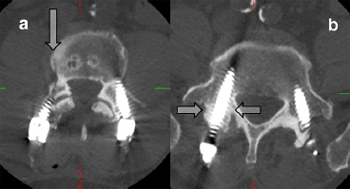

Fig. 9. Axial CT scans showing sclerotic pedicles that may result in the necessity for

screw placement using an open technique. (a) The arrow points towards a Jamshidi

needle tract created when the Jamshidi needle ''hit'' a sclerotic bar of bone between

the pedicle and vertebral body – safe cannulation of the pedicle/vertebral body

could not be achieved and a high-speed drill was used to cannulate the pedicle. (b)

This pedicle (arrows) was sclerotic – Jamshidi placement required an open screw

positioning.

4.6. Sclerotic pedicle – difficult Jamshidi placement in hard pedicles

Pedicles that are sclerotic or osteopetrotic (''ivory bone'') can be

difficult in terms of Jamshidi placement. Advancing a Jamshidi into

these pedicles can be frustrating – rarely the percutaneous technique needs to be abandoned and an open technique with

direct cannulation of the pedicle with a high-speed drill is required

(Fig. 9).